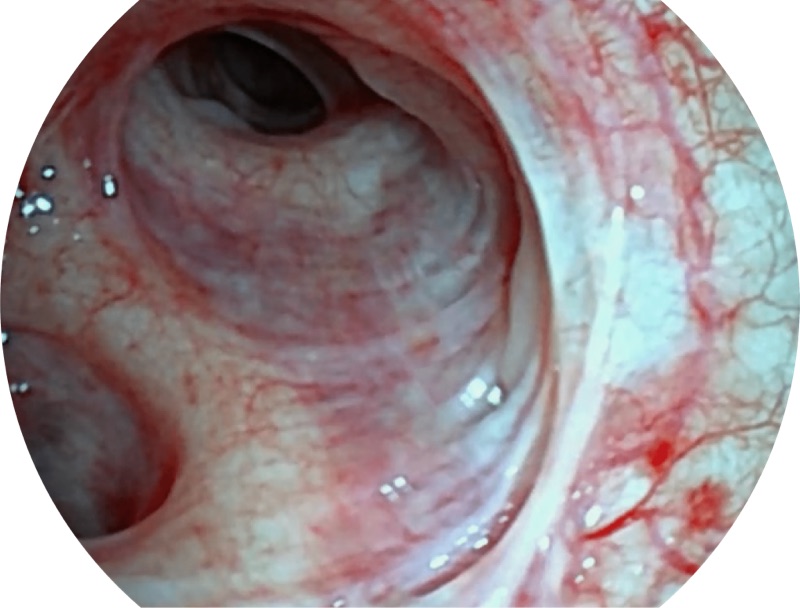

SFI